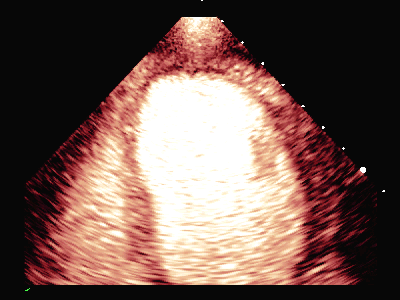

动态图(2)静息状态双平面LVO

负荷前左室壁未见明确节段性运动异常,左室各节段心肌灌注充盈良好。

平板负荷量达89%时,该时患者心率157次/分,出现短阵性室性心动过速,即刻超声造影检查显示:负荷后左室前间隔中段、室间隔心尖段、侧壁中段、心尖段、下壁心尖段、前壁心尖段及心尖帽运动减弱。室间隔心尖段及心尖帽心肌灌注稀疏。

患者休息后检查:左室壁未见明确节段性运动异常,左室各节段心肌灌注充盈良好。